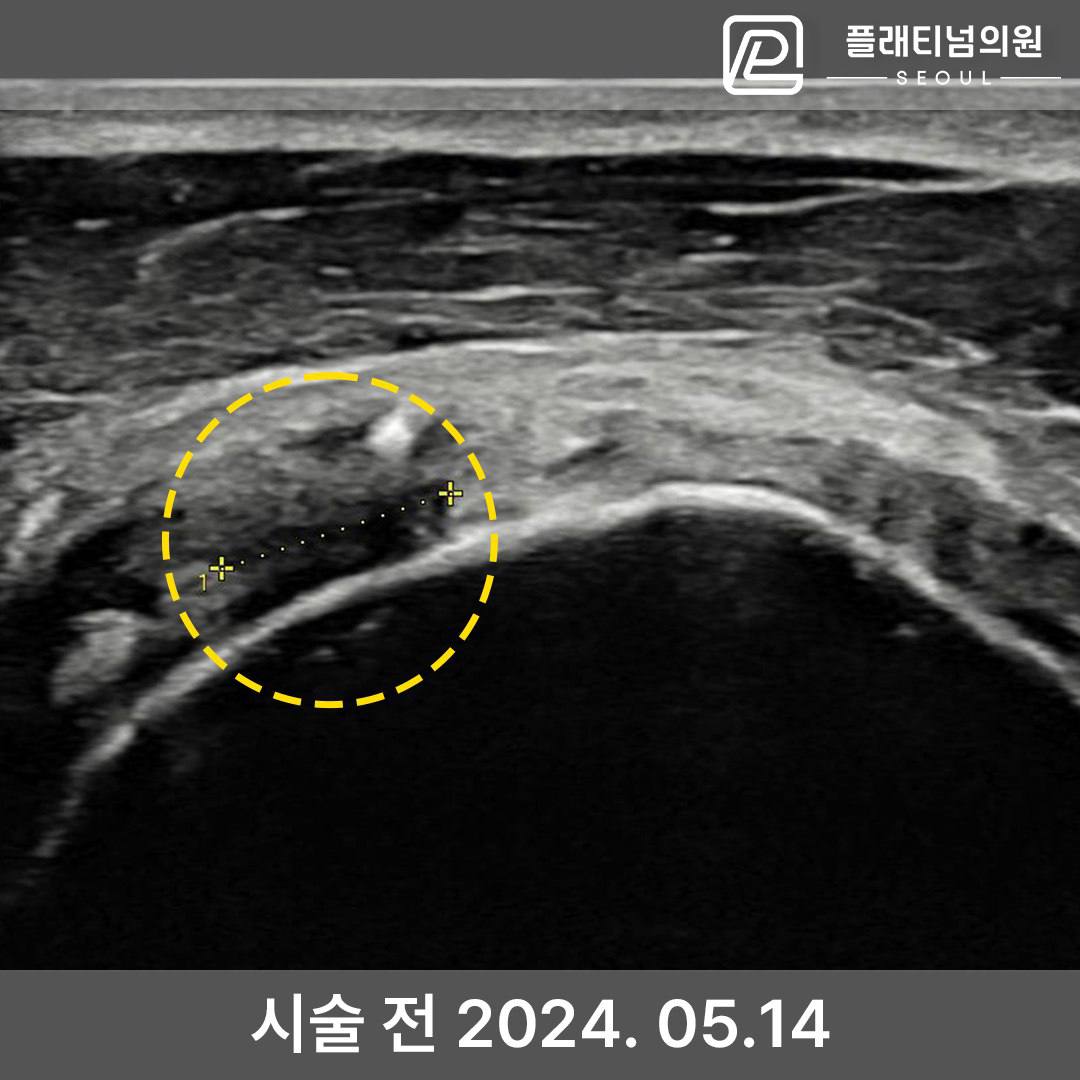

치료 성공사례